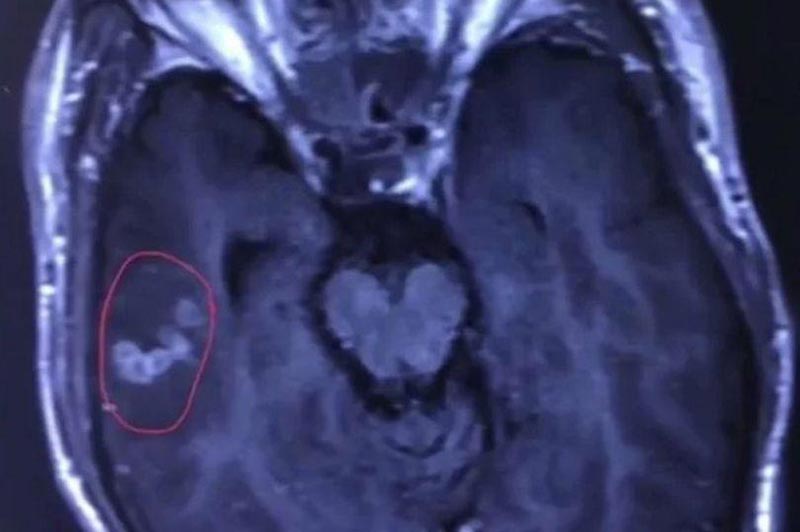

จากการรายงานของเว็บไซต์ไชน่ามอร์นิ่งโพสต์ เมื่อวันที่ 12 สิงหาคม 2561 ระบุว่า ดร.หวังชุนเหลียง แพทย์เจ้าของไข้ ได้เก็บตัวอย่างเลือดของหลิวไปตรวจสอบ และผลปรากฏว่า มีพยาธิตัวตืดชนิด Spirometra Mansoni อาศัยอยู่ในสมองของนายหลิว และเมื่อทำการเอกซเรย์สมองก็พบเห็นพยาธิอย่างชัดเจน ดร.หวังจึงได้จัดการผ่าตัดให้นายหลิวทันที เพราะถ้าปล่อยเอาไว้อาจเป็นอันตรายยิ่งกว่านี้

โดยขณะผ่าตัด ทีมแพทย์พบว่า พยาธิตัวนี้ยังมีชีวิตอยู่ มันขยับตัวดุกดิก ยืด ๆ หด ๆ ว่ายอยู่ในสมองของคนไข้ และเมื่อจัดการนำมันออกมาวัด ก็พบว่ามีความยาวประมาณ 10 เซนติเมตร